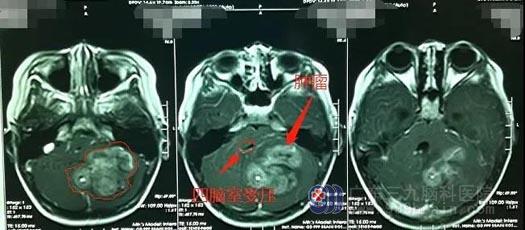

▲菲菲影像检查

我院影像检查显示患儿左侧小脑半球存在占位性病变,大小约为5.4cm*4.1cm*4.0cm。完善相关检查后,鲁明团队为患儿实施了左侧小脑占位病变切除术,手术过程顺利。术后复查MR,患儿颅内的原病灶已被全部切除。